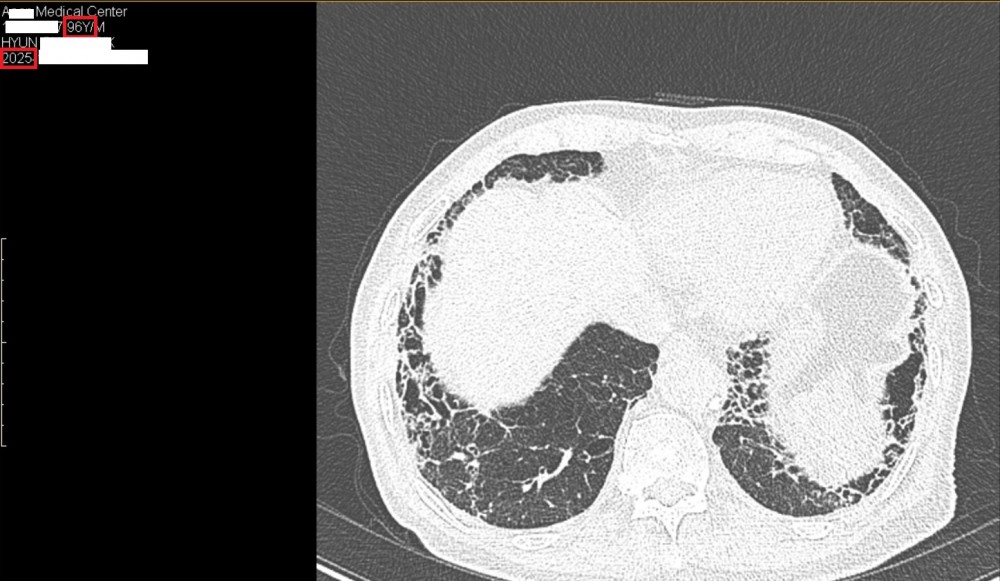

2025년(96세) CT 사진

​폐섬유증 치료 받고 계시는 현00님의 따님께서 선물을 가지고 오셨습니다

2022년부터 숨케어한의원에서 관리 받고 계시는 분입니다

폐섬유증 관련해서는 피레스파 같은 양약을 복용하지 않고 한약만 복용하고 계시는데 잘 관리가 되고 있어서 다행으로 생각하고 있습니다

현재 숨케어한의원에서 폐섬유증 치료 받는 분 중에서 최고령(97세)입니다